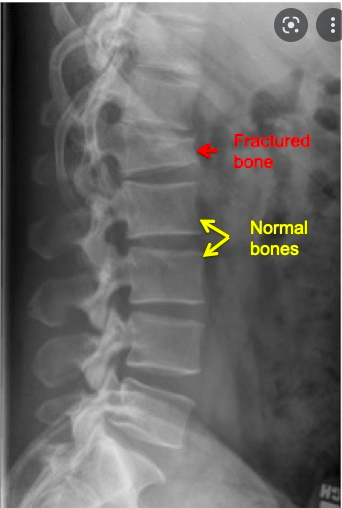

Identify the vertebral fracture(s)

How are vertebral fractures identified on X-ray?

loss in vertebral body height relative to normal adjacent vertebra or relative to